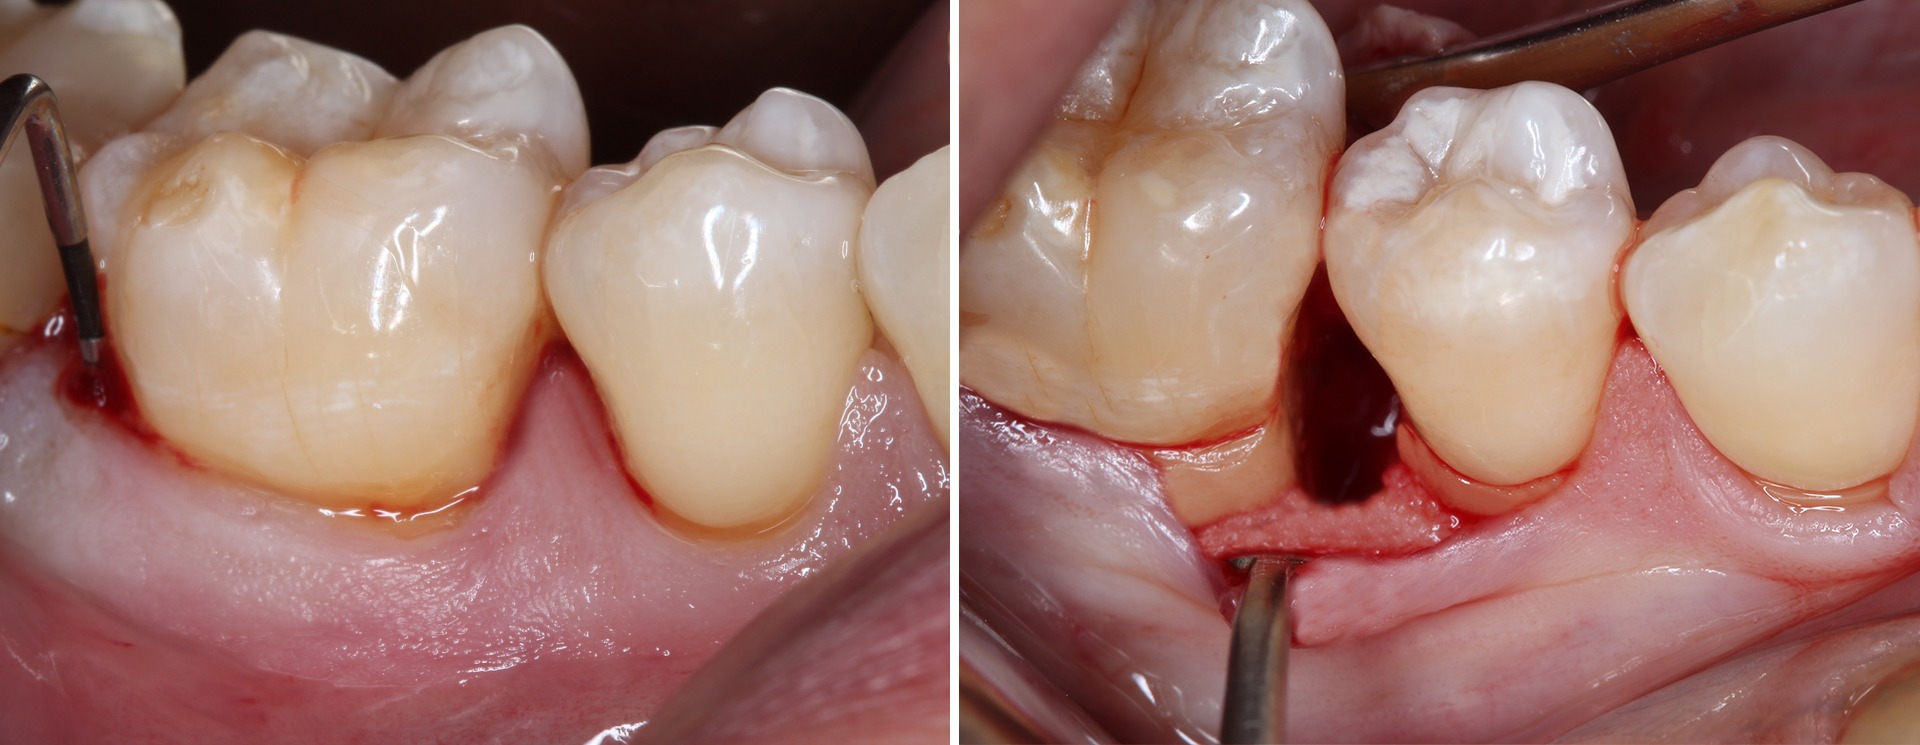

A cirurgia pode ser solução?

Por vezes verifica-se a necessidade de tratamento cirúrgico, que se poderá justificar em casos mais graves e que permitem muitas vezes salvar dentes.